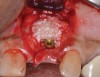

The challenge in removing implants fractured at the connection is primarily the difficulty in using reverse torque instrumentation. This method involves engaging the internal aspect of the implant to be removed. With a fractured implant, this method may cause further fracture, complicating its removal. Most commonly, these implants are removed with hollow, trephine drills. For a trephine to be effective, the inner diameter must be slightly larger than the widest portion of the fractured implant. This ensures that the trephine can move along the entire length of the implant without cutting into it. If the implant is sectioned at it's widest portion, which unfortunately results in significant spreading of titanium debris, a narrower trephine can be utilized to help conserve additional bone. After the threads of the implant body are no longer in contact with the surrounding bone, a small, root elevator is inserted circumferentially to fracture the apical portion of the fixture from the bone below. This is a very delicate procedure, especially when the implant is in close proximity to adjacent teeth or implants, the maxillary sinus, or the inferior alveolar canal. With proper diagnostics, which often include cone-beam computed tomography (CBCT) scans to evaluate the surrounding bone in three dimensions, this can be done safely. Figure 3 depicts an example of an implant that was removed using reverse torque instrumentation and one that was removed using a trephine.

(3.) Two implants removed with two separate techniques. The narrow implant had an abutment that was easily removed, making it possible to engage with a reverse torque device. The wider implant contained a fractured abutment screw and required removal with a trephine. Its wider platform dictated that the trephine fit over this portion, and the osseointegrated bone can be seen attached to the explanted fixture.

Figure 3